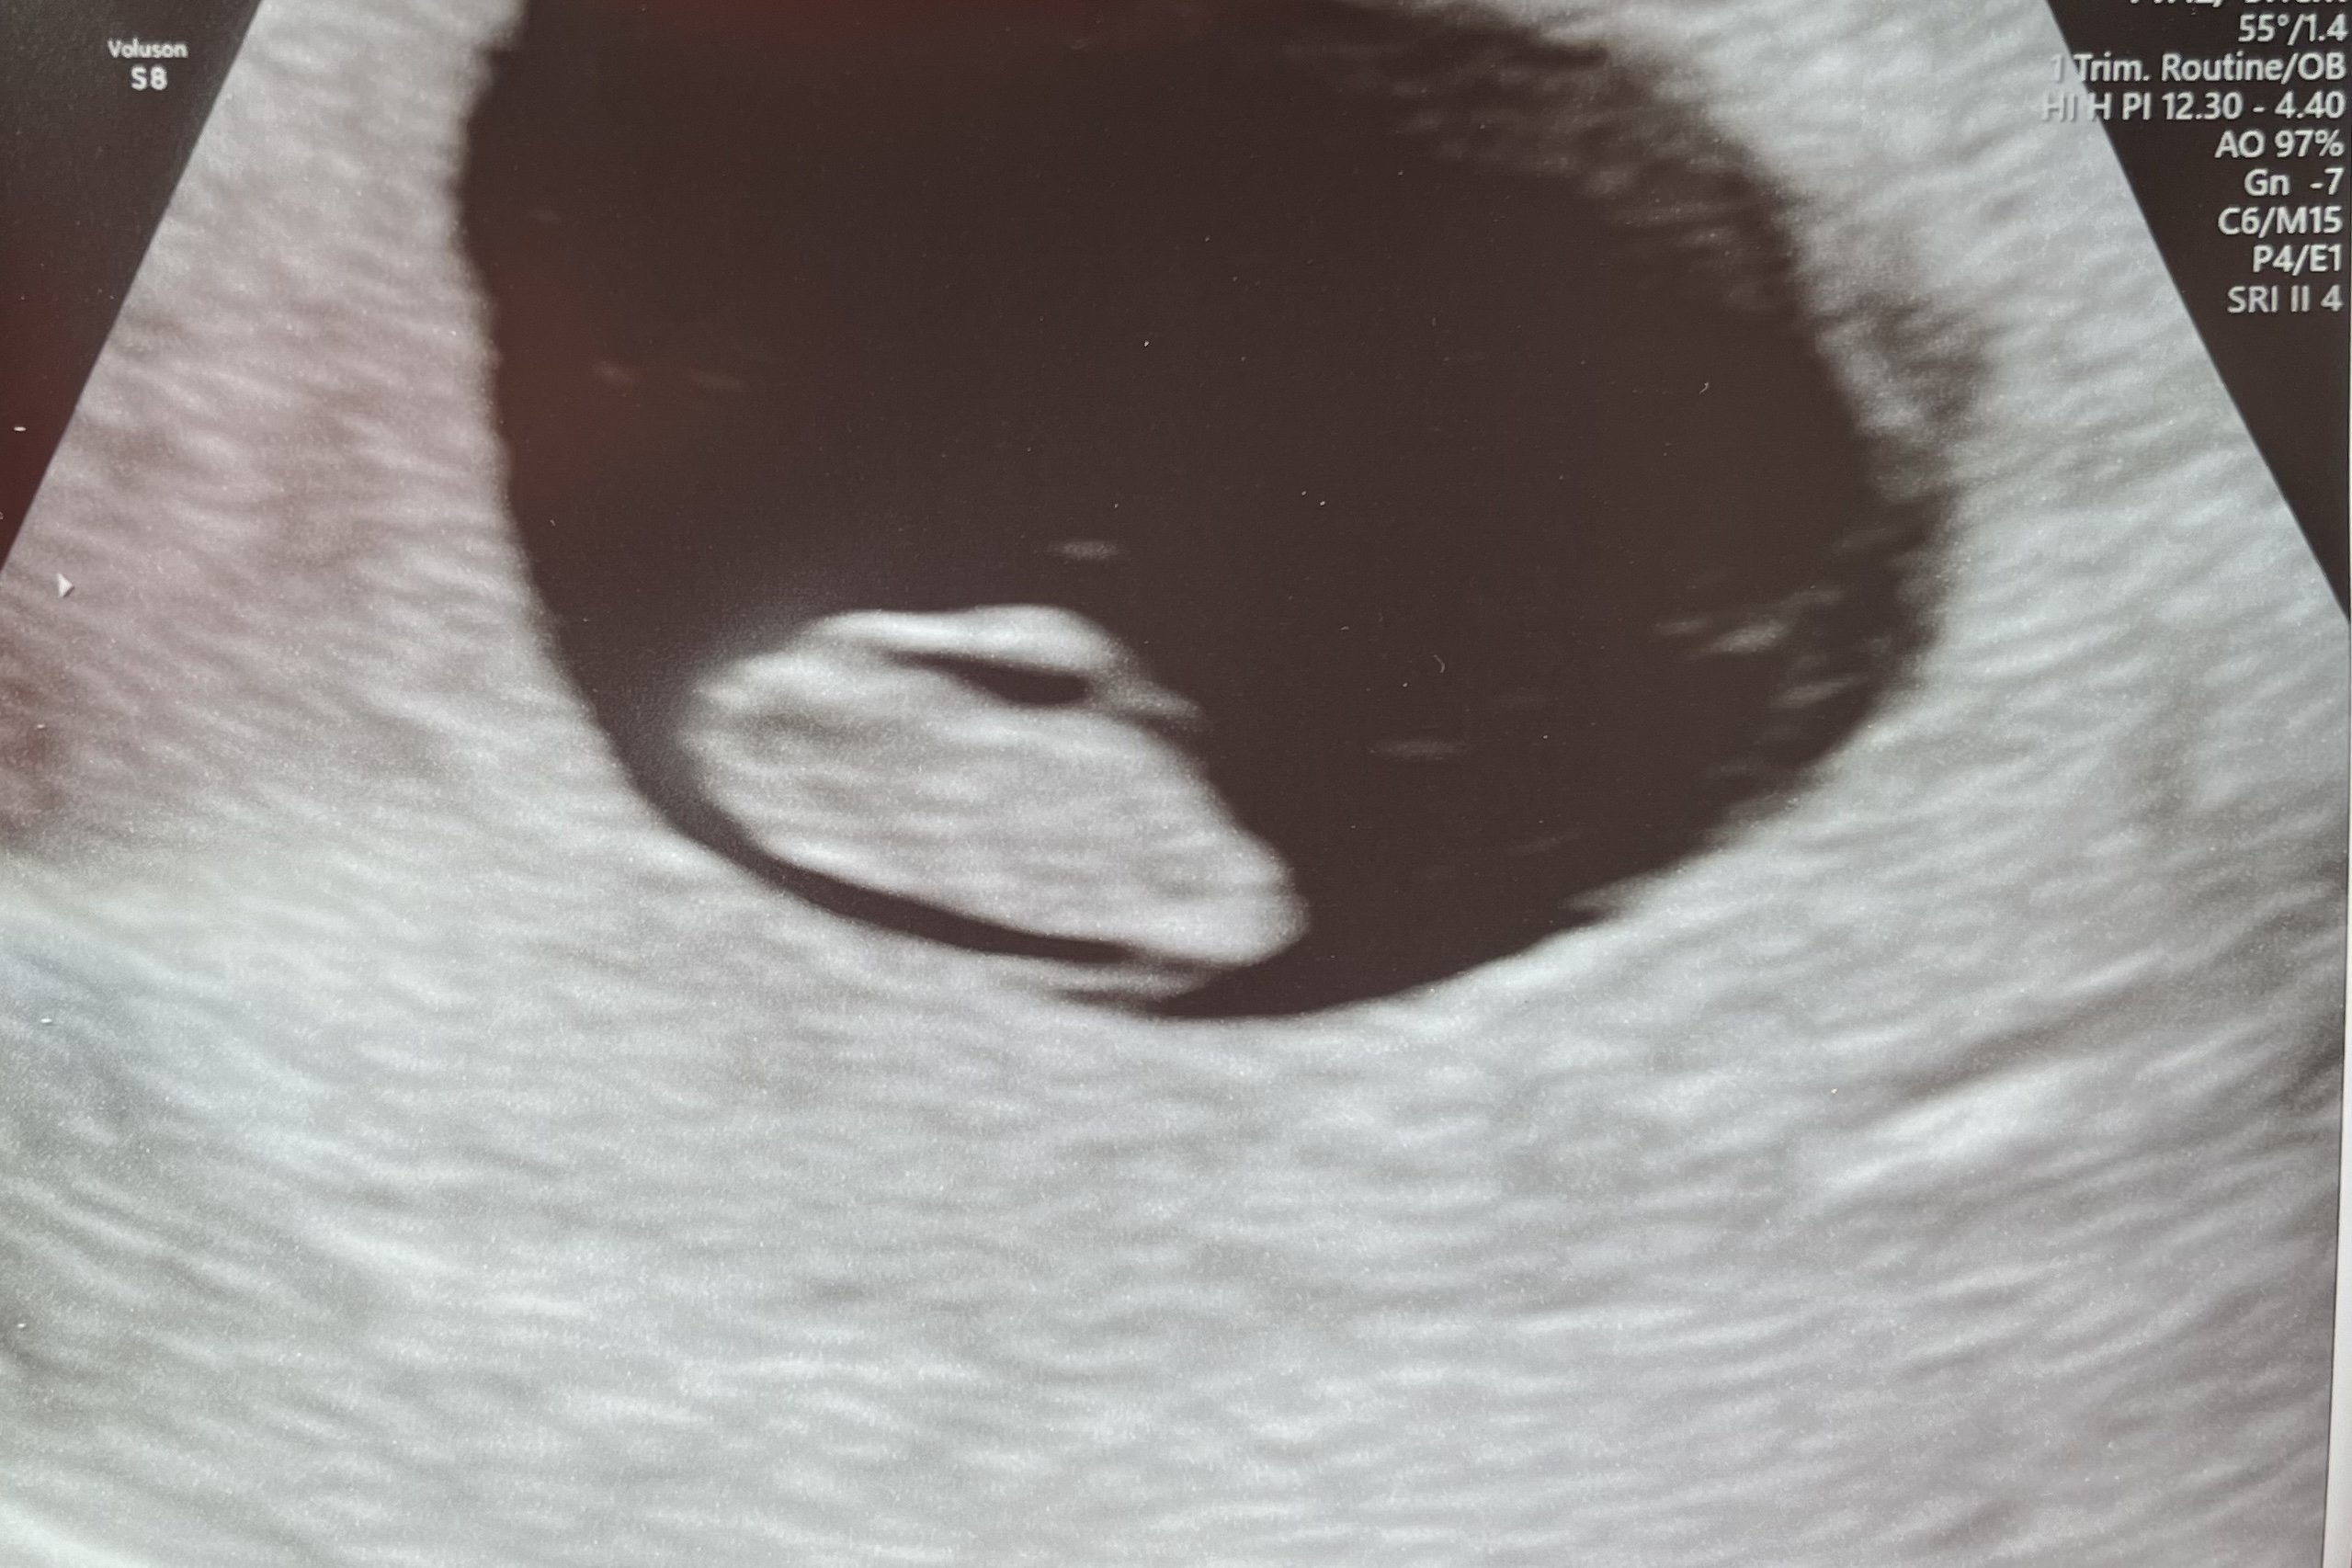

We had an early viability ultrasound due to previous complications. Not much to see at 5 weeks 2 days but everything that they should be able to see is there! Gestational sac and tiny little yolk sac. ❤️